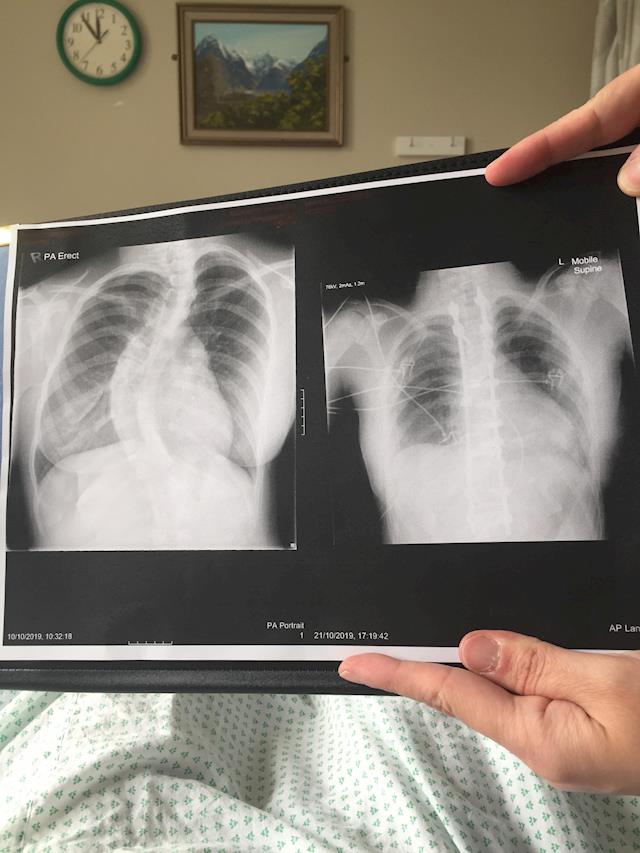

Hi my name is Madison. I am 14 years old and have a large scoliosis curve in my upper back. I have only known about my curve since January 2019 but it has effected my physical ability. I am a very active person but my back is putting a lot of stress and pain on me.

The side effects include reduced lung function due to the pressure the ribs place on the lungs. Therefore we really need your help to get a brace fitted and rehab started. The brace cost is AUD$3600 plus flight costs of $1200 return (need 6 in first year). Physio and chiropractic costs are $150 per week. Rehab is in Sydney and is extra again.

In October I had my surgery. It was a long lead up as we had to drive down to Dunedin Hospital. My surgery ended up taking 9 hours. During my surgery I had an endoscopic release and posterior fusion. My beginning degree was 71degrees but I came out of surgery 13degress. I am now fused from T2-L1 with 2 metal rods and many screws.